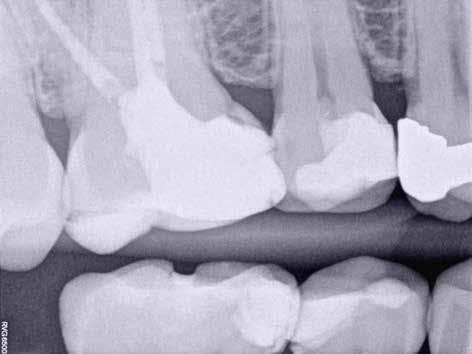

Egy 38 éves nőbeteg a korábban kezelt jobb felső második kisőrlőfogából (1.5) kiinduló mérsékelt fájdalom miatt jelentkezett rendelésünkön. A kórtörténetében jelen panasza szempontjából releváns információ nem szerepelt. A beteg a klinikai vizsgálat során vertikális kopogtatásra enyhe érzékenységet jelzett. A kérdéses fog körül mérhető szondázási mélység és a fogmobilitás fiziológiás volt. Periapicalis röntgenfelvételen egy, a fog gyökércsúcsán túl presszálódott betört gyökérkezelő műszerből származó eszközfragmentumot láttunk (2. a. ábra). A preoperatív CBCT-felvétel a buccalis csontlemez épségét igazolta (2. b-c. ábra). A fog revíziója öt hónappal korábban történt. A már előzőleg gyökérkezelt, gyökértömött, majd revideált 1.5-ös fog esetében a diagnózisunk periodontitis periapicalis symptomatica volt. A periapikális elváltozás kezelése érdekében navigált endodonciai mikrosebészeti beavatkozást végeztünk.

A felső állcsontról intraorális szkent (TRIOS) készítettünk, és az ezáltal kapott STL fájlt (2. d. ábra) a CBCT-felvétel során nyert DICOM fájlokkal a Zirkonzahn.Implant-Planner (Zirkonzahn) szoftverben egyesítettük. A sebészi sablont ebben a programban megterveztük, majd a Meshmixer (Autodesk) szoftver se-

gítségével tovább módosítottuk. Az így kapott sebészi sablon egyértelműen meghatározta a periapikális terület eléréséhez szükséges csontablak határait (2. e-f. ábra) Helyi érzéstelenítést követően teljes vastagságú mucoperiostealis lebenyt képeztünk, majd a buccalis csont feltárását követően (2. g. ábra) a sablon segítségével bejelöltük a preparálandó csontablak határait (2. h. ábra). A csontablak kialakítása során Piezotome CUBE LED kézi-darabot alkalmaztunk, majd a leemelését követően a betört eszközt megkerestük (2. i. ábra) és eltávolítottuk (2. j. ábra). A rezekciót ultrahangos megmunkáló fejekkel (ACTEON) végeztük, majd retrográd preparáció következett.

A retrográd gyökértömés elkészítése során TotalFill BC RRM Fast Set Putty-t (FKG) használtunk (2. k. ábra). A lebeny széleit 5/0-s Prolene varratokkal egyesítettük (2. l. ábra). A varratok a műtétet követően 72 órával kerültek eltávolításra. A beteg két évvel később kontrollröntgen készítése céljából érkezett rendelőnkbe. A vizsgálat során a fog tünetmentesnek és funkcióképesnek bizonyult (2. m. ábra).